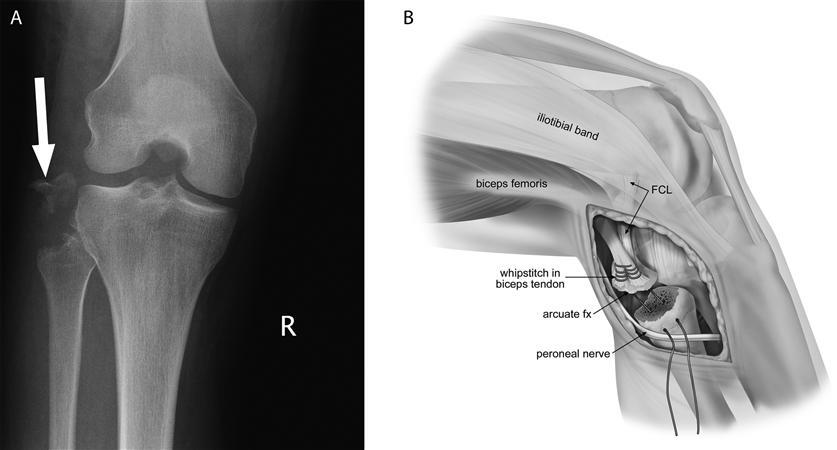

A

avulsion fracture of the fibula (arcuate fracture ) or femoral condyle